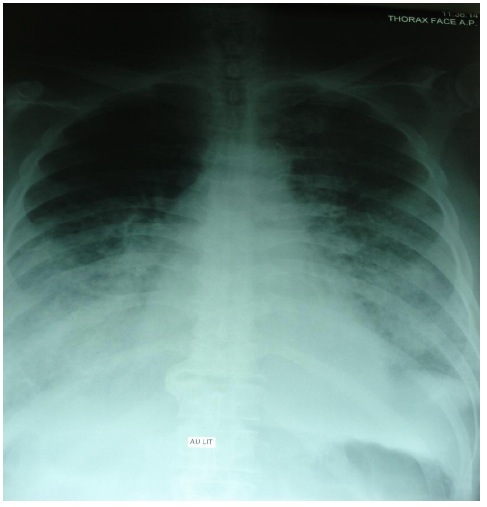

Quelques heures après l’accident, on notait la survenue brutale d’une dyspnée avec chute de la saturation artérielle en oxygène à 88% malgré une oxygénation à 5 litres par minutes. L’examen physique révélait une cyanose discrète des extrémités, des expectorations saumonées, une tachycardie à 120 battements par minutes et des gros crépitants en marée montante au niveau des deux champs pulmonaires. On n’avait noté ni galop ni souffle cardiaque. La radiographie pulmonaire avait montré des opacités alvéolaires bilatérales prédominant au niveau hilaire (figure 2).